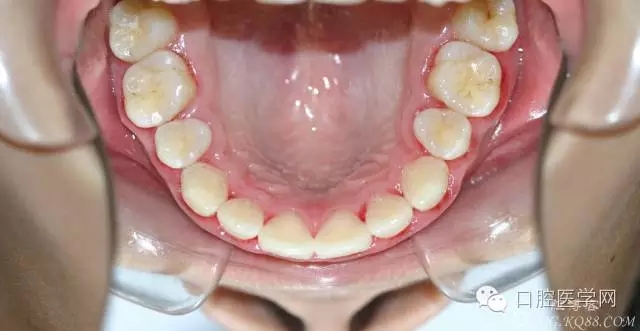

正畸查:替牙合。第一恒磨牙中性合。上牙弓尖圓型下牙弓方圓型。前牙覆合3度覆蓋7.5mm。下前牙咬到上舌側(cè)牙齦。上頜擁擠4.0mm,下頜擁擠

3.0mm。上頜稍前突下頜后縮,上下唇前突,上前牙覆蓋下唇,下唇外翻。面下三分之一過(guò)短,頦唇溝明顯,開(kāi)唇露齒,頦饜窩明顯。顳下頜關(guān)節(jié)開(kāi)閉口無(wú)彈響,無(wú)壓痛,開(kāi)口型開(kāi)口度正常。